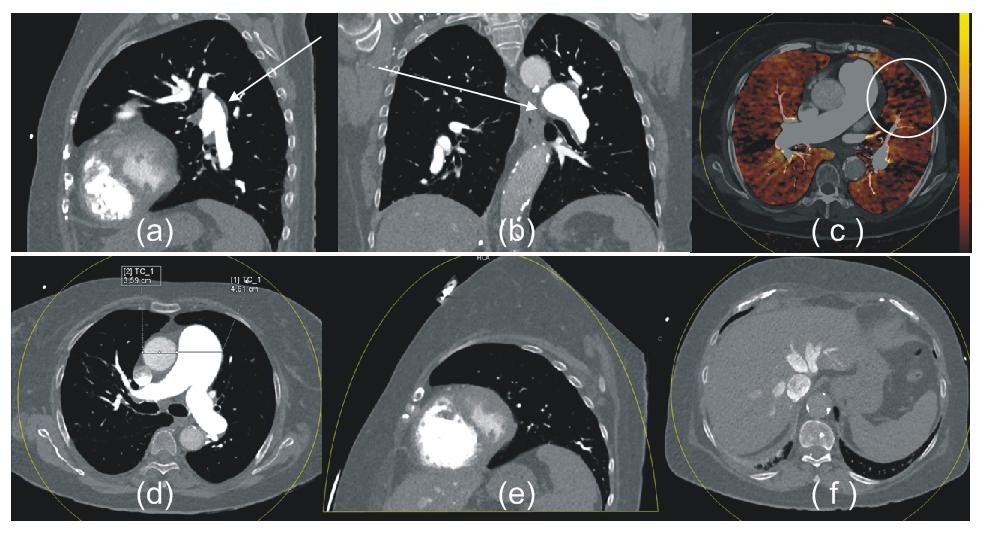

The normal lung shows homogeneous distribution of iodine in the entire parenchyma, whereas in patients with occlusive pulmonary emboli, iodine perfusions maps show sharply delineated triangular- shaped subpleural iodine defect areas corresponding to embolism [1] (Figure 1).

Contrast enhancement defects that are consistent with PE include those that are peripherally located, wedge- sharped and in a segmental or lobar distribution (Figure 4,5,6 and 7).

DECT angiography not only depicts the contrast enhancement defects resulting from acute PE, but also shows contrast enhancement defects associated with chronic clots (Figure 9) [2,7,8].

Pulmonary arterial hypertension may be idiopathic or arise in association with chronic pulmonary thromboembolism. Chronic thromboembolic pulmonary hypertension affects approximately 4% of patients with acute pulmonary embolism. The CTPA findings of chronic thromboembolic pulmonary hypertension include parenchymal and vascular signs.

The characteristic morphologic CT features of chronic pulmonary arterial hypertension (PH) are dilatation of the pulmonary artery trunk, the diameter of which frequently exceeds that of the ascending aorta; dilatation of the right and left main pulmonary arteries; abrupt narrowing and tapering of the peripheral pulmonary vessels; right ventricular hypertrophy; and right ventricular and atrial enlargement with inversion of the interventricular septum and dilatation of the tricuspid valve annulus (Figure 10) [6-8].